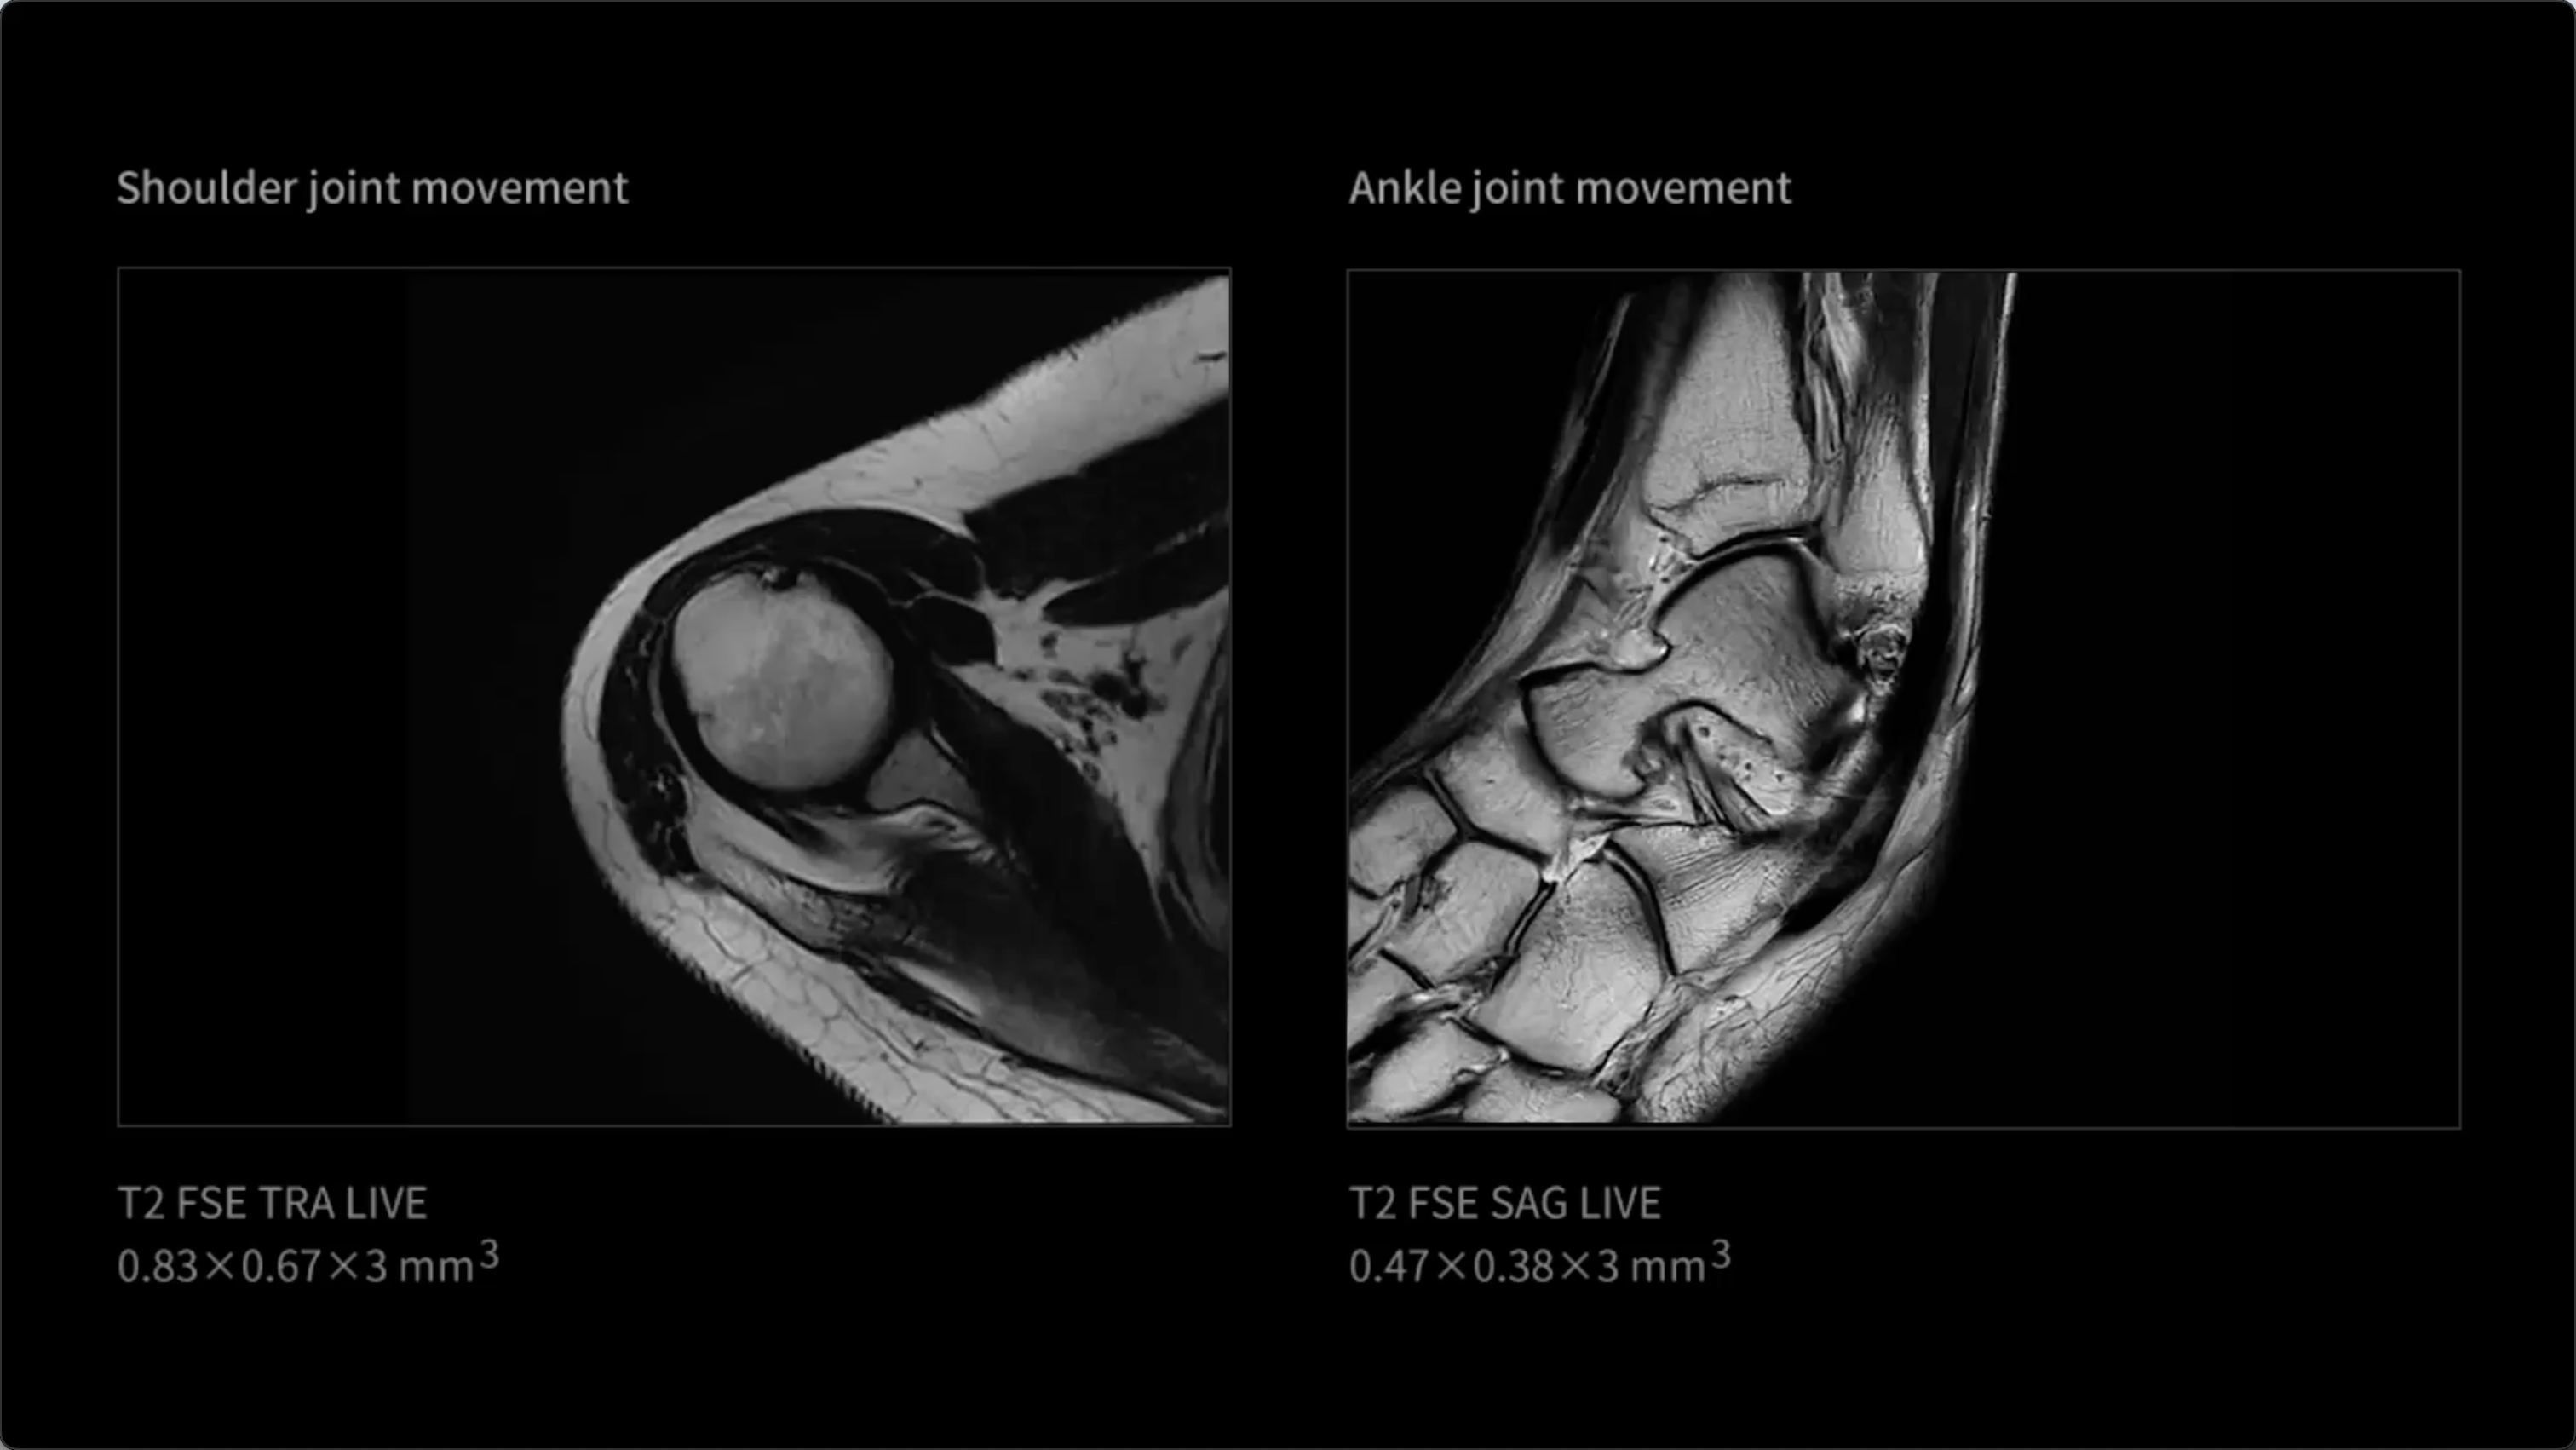

uMR Ultra introduces groundbreaking LIVE Imaging, enabling comprehensive whole-body 'photography' that continuously captures high-definition visualization of both anatomical structures and functional tissue activity. The LIVE Imaging technology not only delivers exceptional frame-by-frame clarity, but also provides coherent dynamic information that unlocks a new diagnostic dimension. This represents significant potential for improved evaluation of dynamic anatomical regions including the gastrointestinal tract, pelvis, joints, and nervous system, among others.